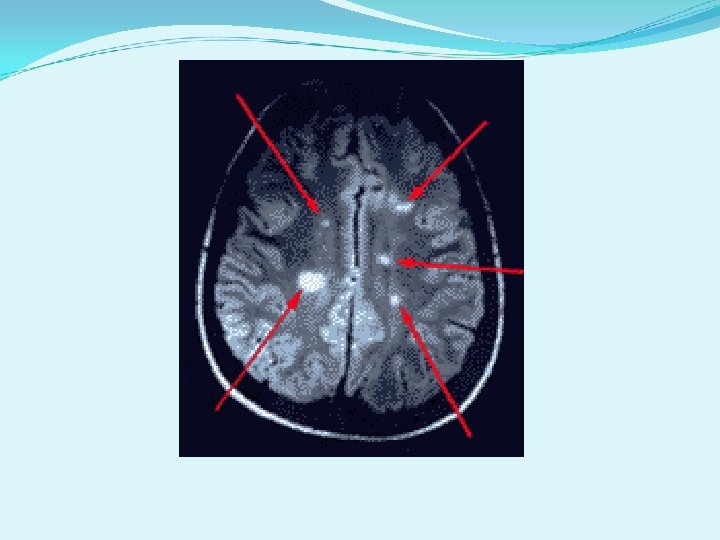

Radiological Findings

What is Multiple Sclerosis? q It is an Auto Immune Disease which is when the body starts to destroy itself. q It is a life-long disease with no cure. q In MS, the body attacks and destroys the fatty tissue called myelin that insulates an axon/nerve, and is called demyelination. q If damage is severe it can also destroy the nerve/axon itself. q MS affects the central nervous system and inflames the white matter in the brain which creates plaques.

Disease Overview: Multiple Sclerosis (MS) is an inflammatory disease of the Central Nervous System (CNS) affecting the brain and spinal cord. Predominantly, it is a disease of the "white matter" tissue. The white matter is made up of nerve fibers which are responsible for transmitting communication signals both internally within the CNS and between the CNS and the nerves supplying rest of the body.